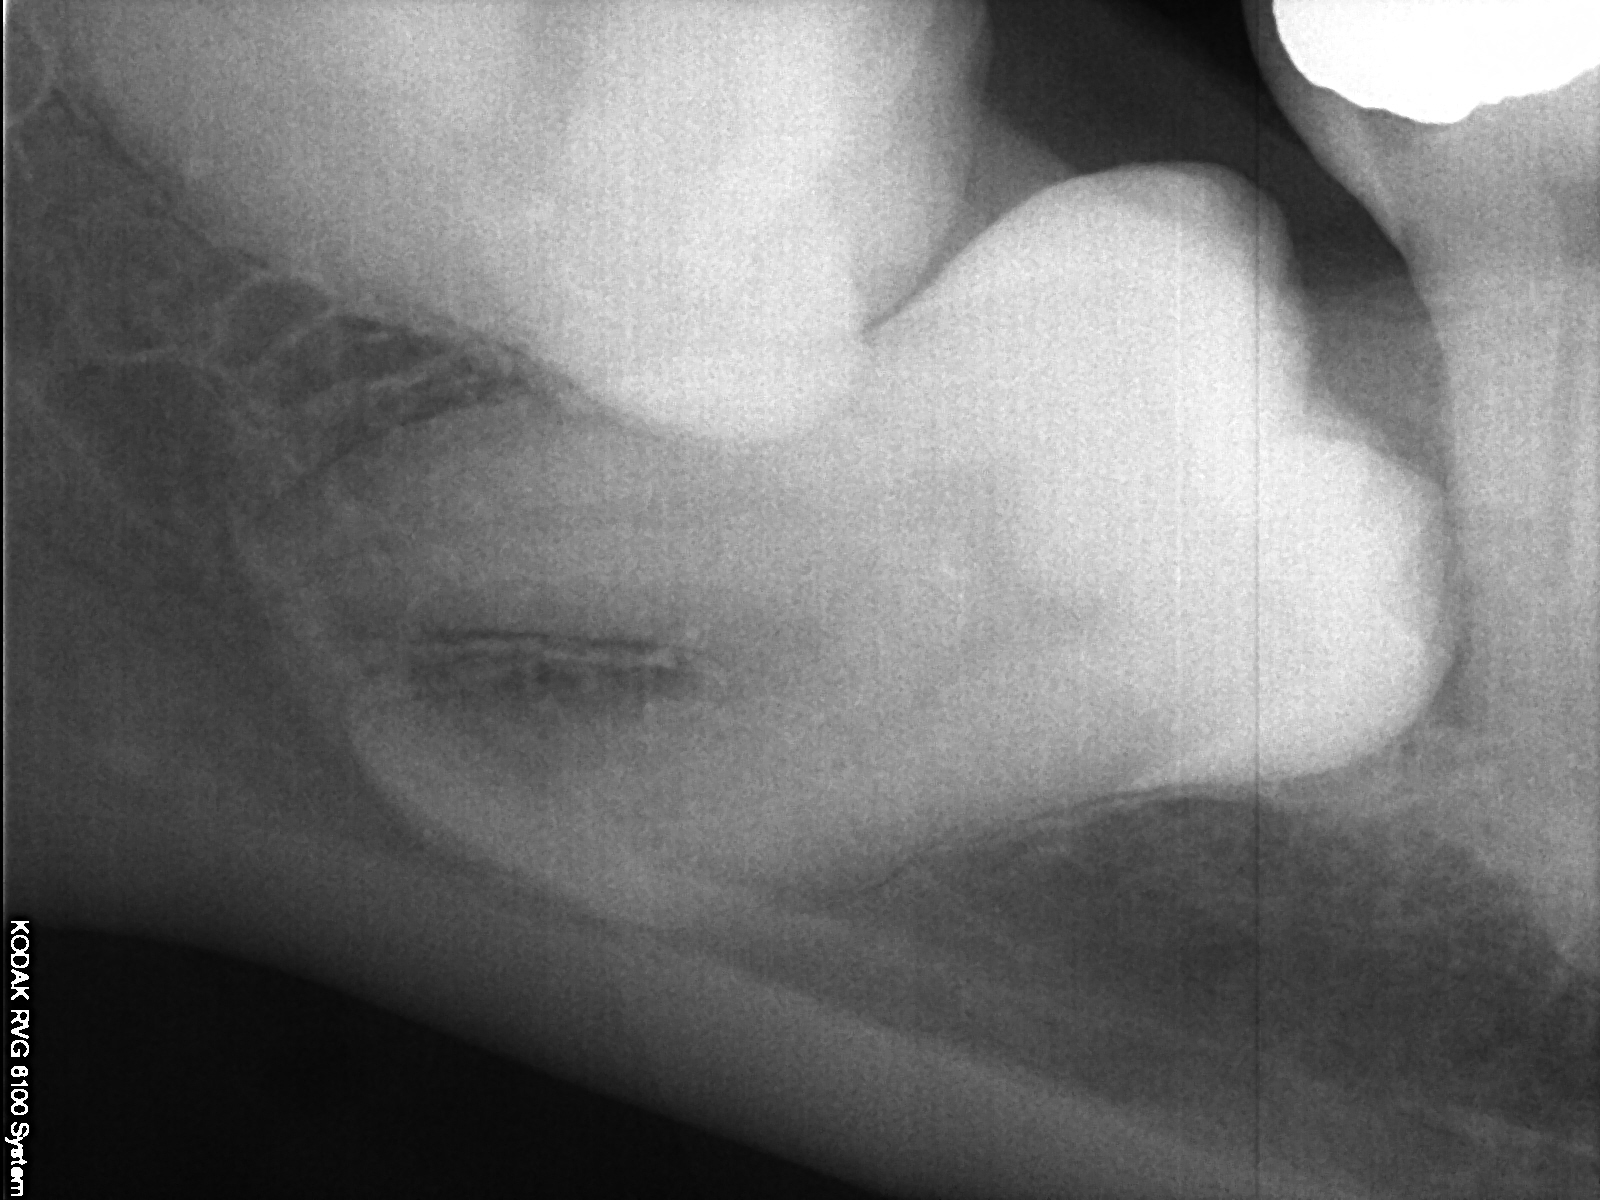

Radiografie per- e post-chirurgiche di un caso particolare di inclusione contemporanea di secondo molare inferiore e dente del giuzio.

Rx pre-operatoria. Si noti il dente del giudizio orizzontale posto superiormente ed il secondo molare anch'esso orizzontale posto più profondamente. In trasparenza è possibile rilevare il canale mandibolare che corre parallelamente al dente più profondo.